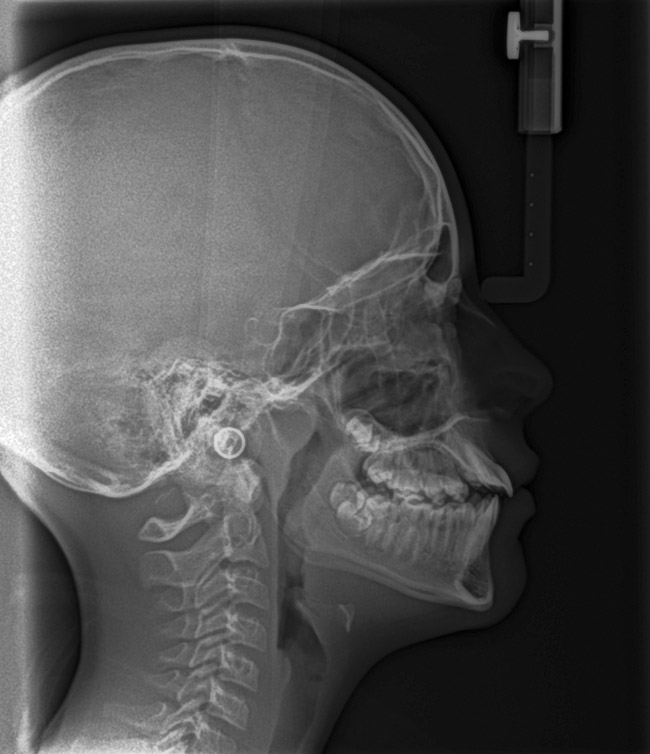

The pattern for bone growth resides not in the bone itself but rather in the soft tissue and muscle that encase the bone.42 Oral-facial muscle tone and tongue tonicity create a framework for normal development of the nasomaxillary complex and mandible.43 SDB is noted in children with pathologic hypotonia of facial and tongue muscles. Children born with a normal palate and oral-facial hypotonia will develop a high, narrow palate over the first year of life (Figure 3 and Figure 4). Children born with a high, narrow palate have hypotonia at birth. These myofunctional changes may be detected in utero.43

Instinctively, clinicians have concentrated on the mandible when discussing airway dimensions. However, the maxilla appears to be the more important arch in determining upper airway dimensions in OSA patients.45 The distance from A point (most posterior point in the concavity of the anterior maxilla) to Porion vertical (vertical line drawn from the most superior part of the external auditory meatus) was the most contributory cephalometric marker for airway patency. Appropriate positioning of the maxilla opens the velopharyngeal and orophayngeal airways. Additionally, proper maxillary positioning enhances mandibular growth. Thus, the lack of facial muscle activity and ideal tongue tone constrains the premaxilla, producing an abnormal airway dimension and amplifying the threat of SDB.

Tonsils and adenoids should be judged against the relative size of the airway rather than the absolute size of the lymphoid tissue46 (Figure 5 and Figure 6). Adenoids are located at the posterior of the nasal cavity on the roof of the nasopharynx (Figure 7). The normal distance from the adenoids to the soft palate for an acceptable airway should be at least 12 mm. For each millimeter decrease, the odds of the child snoring increase 1.61 times. Mouth breathers typically show a smaller upper airway dimension as well.47 The adenoid and tonsillar obstruction creates the trigger, but the deviate facial and neck muscle recruitment and tongue hypotonia cause the maldevelopment.48

The point of obstruction tends to determine the type of skeletal impact. Nasal obstruction from enlarged turbinates, blocked ostium maxillare, deviated septum, or nasal valve stenosis creates Angle occlusions of Class I, II, and III equally (Figure 8). The maxilla in these cases is positioned posteriorly and the mandible is posterior-inferior. The facial type is most commonly dolicocephalic. Blockage of the airway predominately by the adenoids will create growth patterns that yield mostly Class II occlusions and anterior open bite with both jaws located posterior-inferiorly. Facial type is again dolicocephalic with the typical long-thin “adenoidal” face49 (Figure 9 through Figure 12). If the tonsillar tissue is responsible for the airway obstruction, the tongue will have an abnormal resting posture. Class III occlusions will be more common with the maxilla normal or posterior placed (Figure 13 through 15). The tongue may direct the mandible anteriorly or, because the tongue is not in the roof of the mouth driving A point anterior, the maxilla will become bimaxillary retrusive.50 In some cases, the anterior posture of the tongue will create an open bite. This is incorrectly referred to as a tongue thrust. The impact from a thrust does not alter the tooth position. Long-term, low forces cause tooth movement. The posture of the tongue against or between the anterior teeth due to the excessive tonsillar size creates the open bite (Figure 16 and Figure 17). Facial types in this group are more brachyfacial. Lastly, if the airway is blocked through a combination of factors, the Angle classification will be either Class II or III. The maxilla will be in a normal location and the mandible will be the affected arch (Figure 18). These craniofacial changes are not restricted to OSA; all SDB will create unique alterations depending on the patient compensation. Children with UARS have been reported to display high, narrow palates, dolicofacial form, and a Class II malocclusion, indicative of largely adenoidal blockage.51